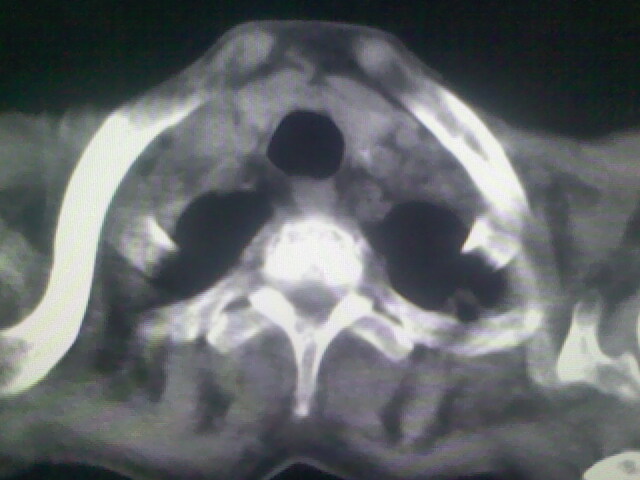

1)考虑右肺上叶周围型肺癌并纵隔及右颈部淋巴结转移,肝脏多发性转移。2)肺气肿。3)冠状动脉及主动脉钙化。

1)考虑右肺上叶周围型肺癌并纵隔及右颈部淋巴结转移,肝脏多发性转移。2)肺气肿。3)冠状动脉及主动脉钙化。支持!另:胃内病变不好确定,建议行胃镜!

1、右肺上叶周围型肺癌并纵隔、颈部淋巴结转移,肝多发转移灶。

支持右肺上叶周围型肺癌伴肝内多发转移.胃建议充盈后重扫描.慢性支气管炎伴肺气肿.